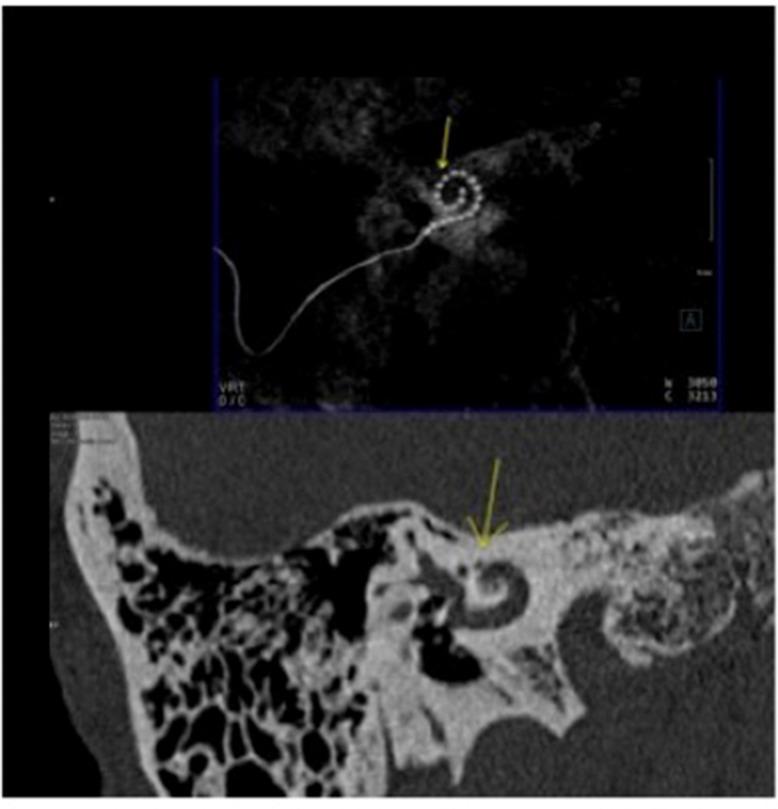

The cochlear implant is an implanted auditory prosthesis that can restore severe and profound hearing loss. About 20% of patients with congenital sensorineural hearing loss have a malformation of the inner ear. These abnormalities must be investigated before a cochlear implant because they can lead to intra and postoperative complications and/or anomalies. Most labyrinthine malformations are well known; some are less frequent and can be underdiagnosed at the preoperative computed tomography. This report presents the case of bilateral cochlear-facial dehiscence, bony dehiscence between the facial nerve labyrinthine segment, and cochlear basal turn. In our 56-year-old patient, this malformation was misdiagnosed before the cochlear implant and revealed afterward because of abnormal facial nerve stimulation during intraoperative electrophysiological checking.

人工耳蜗是一种可植入的听觉假体,能够恢复重度和极重度听力损失。约20%的先天性感音神经性听力损失患者存在内耳畸形。在植入人工耳蜗之前必须对这些异常情况进行检查,因为它们可能导致术中及术后并发症和/或异常。大多数内耳畸形是众所周知的;有些则较少见,在术前计算机断层扫描时可能漏诊。本报告介绍了一例双侧耳蜗-面神经裂缺的病例,即面神经迷路段与耳蜗底转之间的骨质裂缺。在我们这位56岁的患者中,这种畸形在人工耳蜗植入前被误诊,后来由于术中电生理检查时面神经刺激异常而被发现。